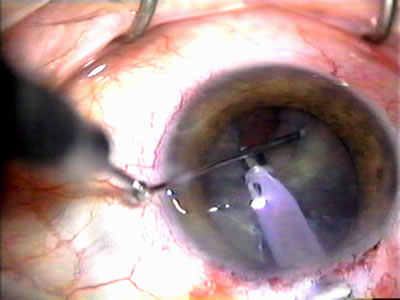

Fig. 2. Wound modulation and revision. A. MMC decreases the likelihood of bleb failure in high-risk eyes undergoing combined cataract and glaucoma surgery. Overusage of this potent cytotoxic drug should be avoided owing to a myriad of problems related to the formation of an avascular bleb. B. Office-based laser revision of the operative wound allows for increased postoperative flexibility with less complications. The correct number and tension of scleral flap sutures allows the surgeon to strive for a safe immediate postoperative IOP range. When fibrosis occurs at approximately 1 week, suturelysis or release of sutures increases filtration while avoiding unwanted hypotony.